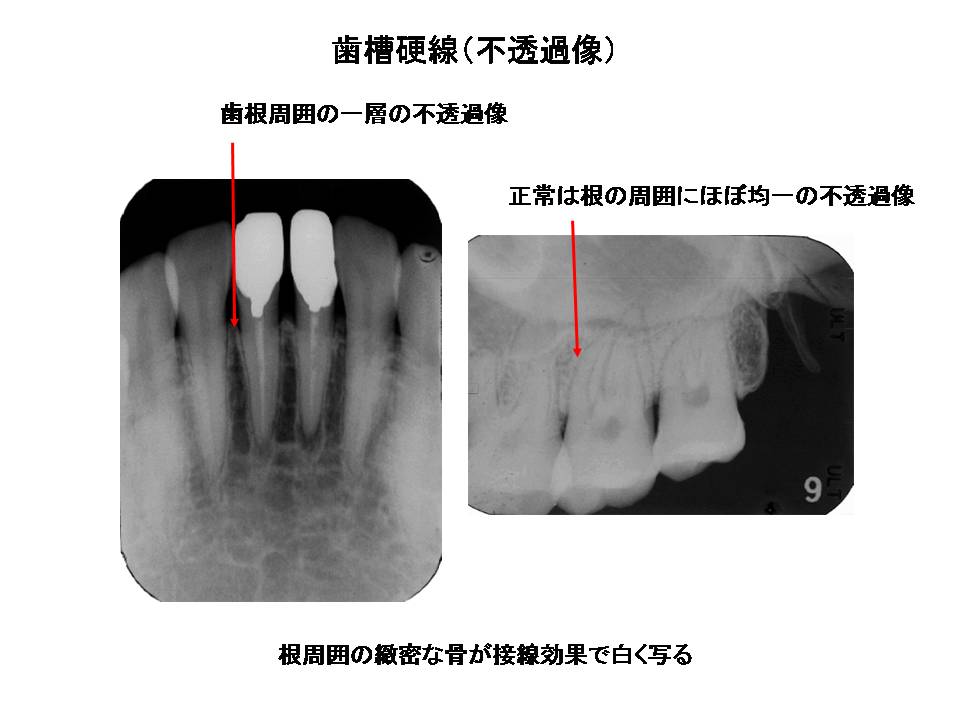

口内法(二等分法・咬合法)撮影の解剖